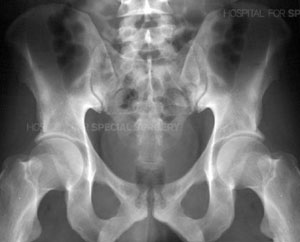

Radiograph of a normal pelvis